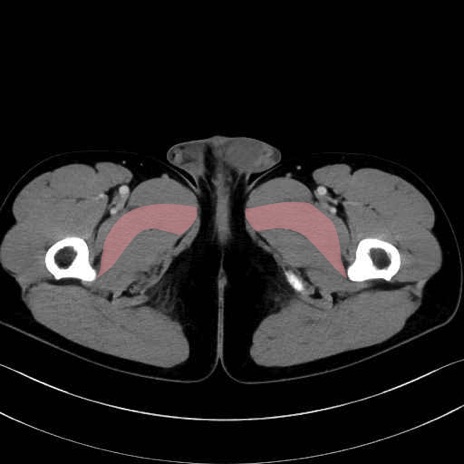

短内転筋(Adductor brevis) のCT画像の解剖

短内転筋 (Adductor brevis)